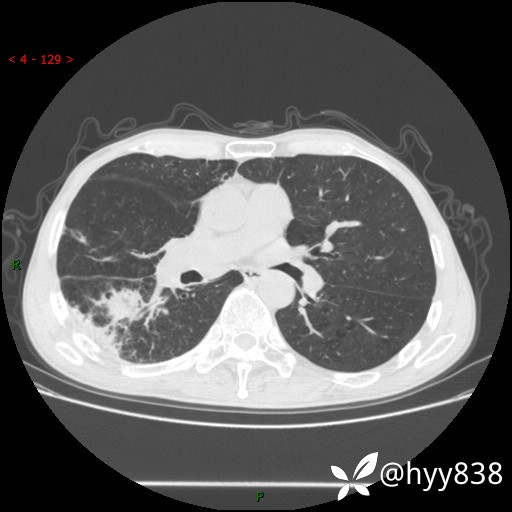

老年男性,肺团片状占位+体重下降,肿瘤 VS 真菌 VS 细菌,看看你的意见--结果公布~

简要病史:患者7天前无明显诱因出现咳嗽咳痰,咳绿色、褐色痰,吸烟后加重,伴心慌、胸闷,无畏寒发热,无头晕头痛,无鼻塞流涕,无痰中带血及咯血,无胸痛、呼吸困难,无全身酸痛,为求进一步诊治于我院就诊,门诊完善胸部CT提示“右下肺团片状影,考虑肿瘤?感染?”,门诊以“咳嗽待查”收住入院。 起病以来,患者精神、饮食、睡眠尚可,大、小便正常,体力下降,体重下降8斤。空腹血糖:6.42mmol/L。

辅助检查:CT

临床诊断:肿瘤?感染?

讨论:病变性质?

静脉期